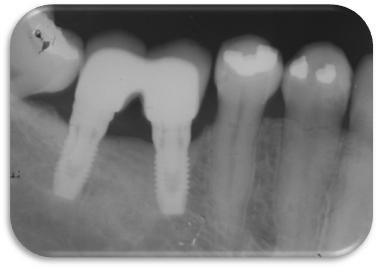

Imagem do artigo

Figura 6. Radiografia periapical do implante instalado na região do 36 após 8 anos em função. Importante observar que a perda óssea peri-implantar limita-se à porção usinada dos implantes e que esta perda é provavelmente devido à readaptação das distâncias biológicas.